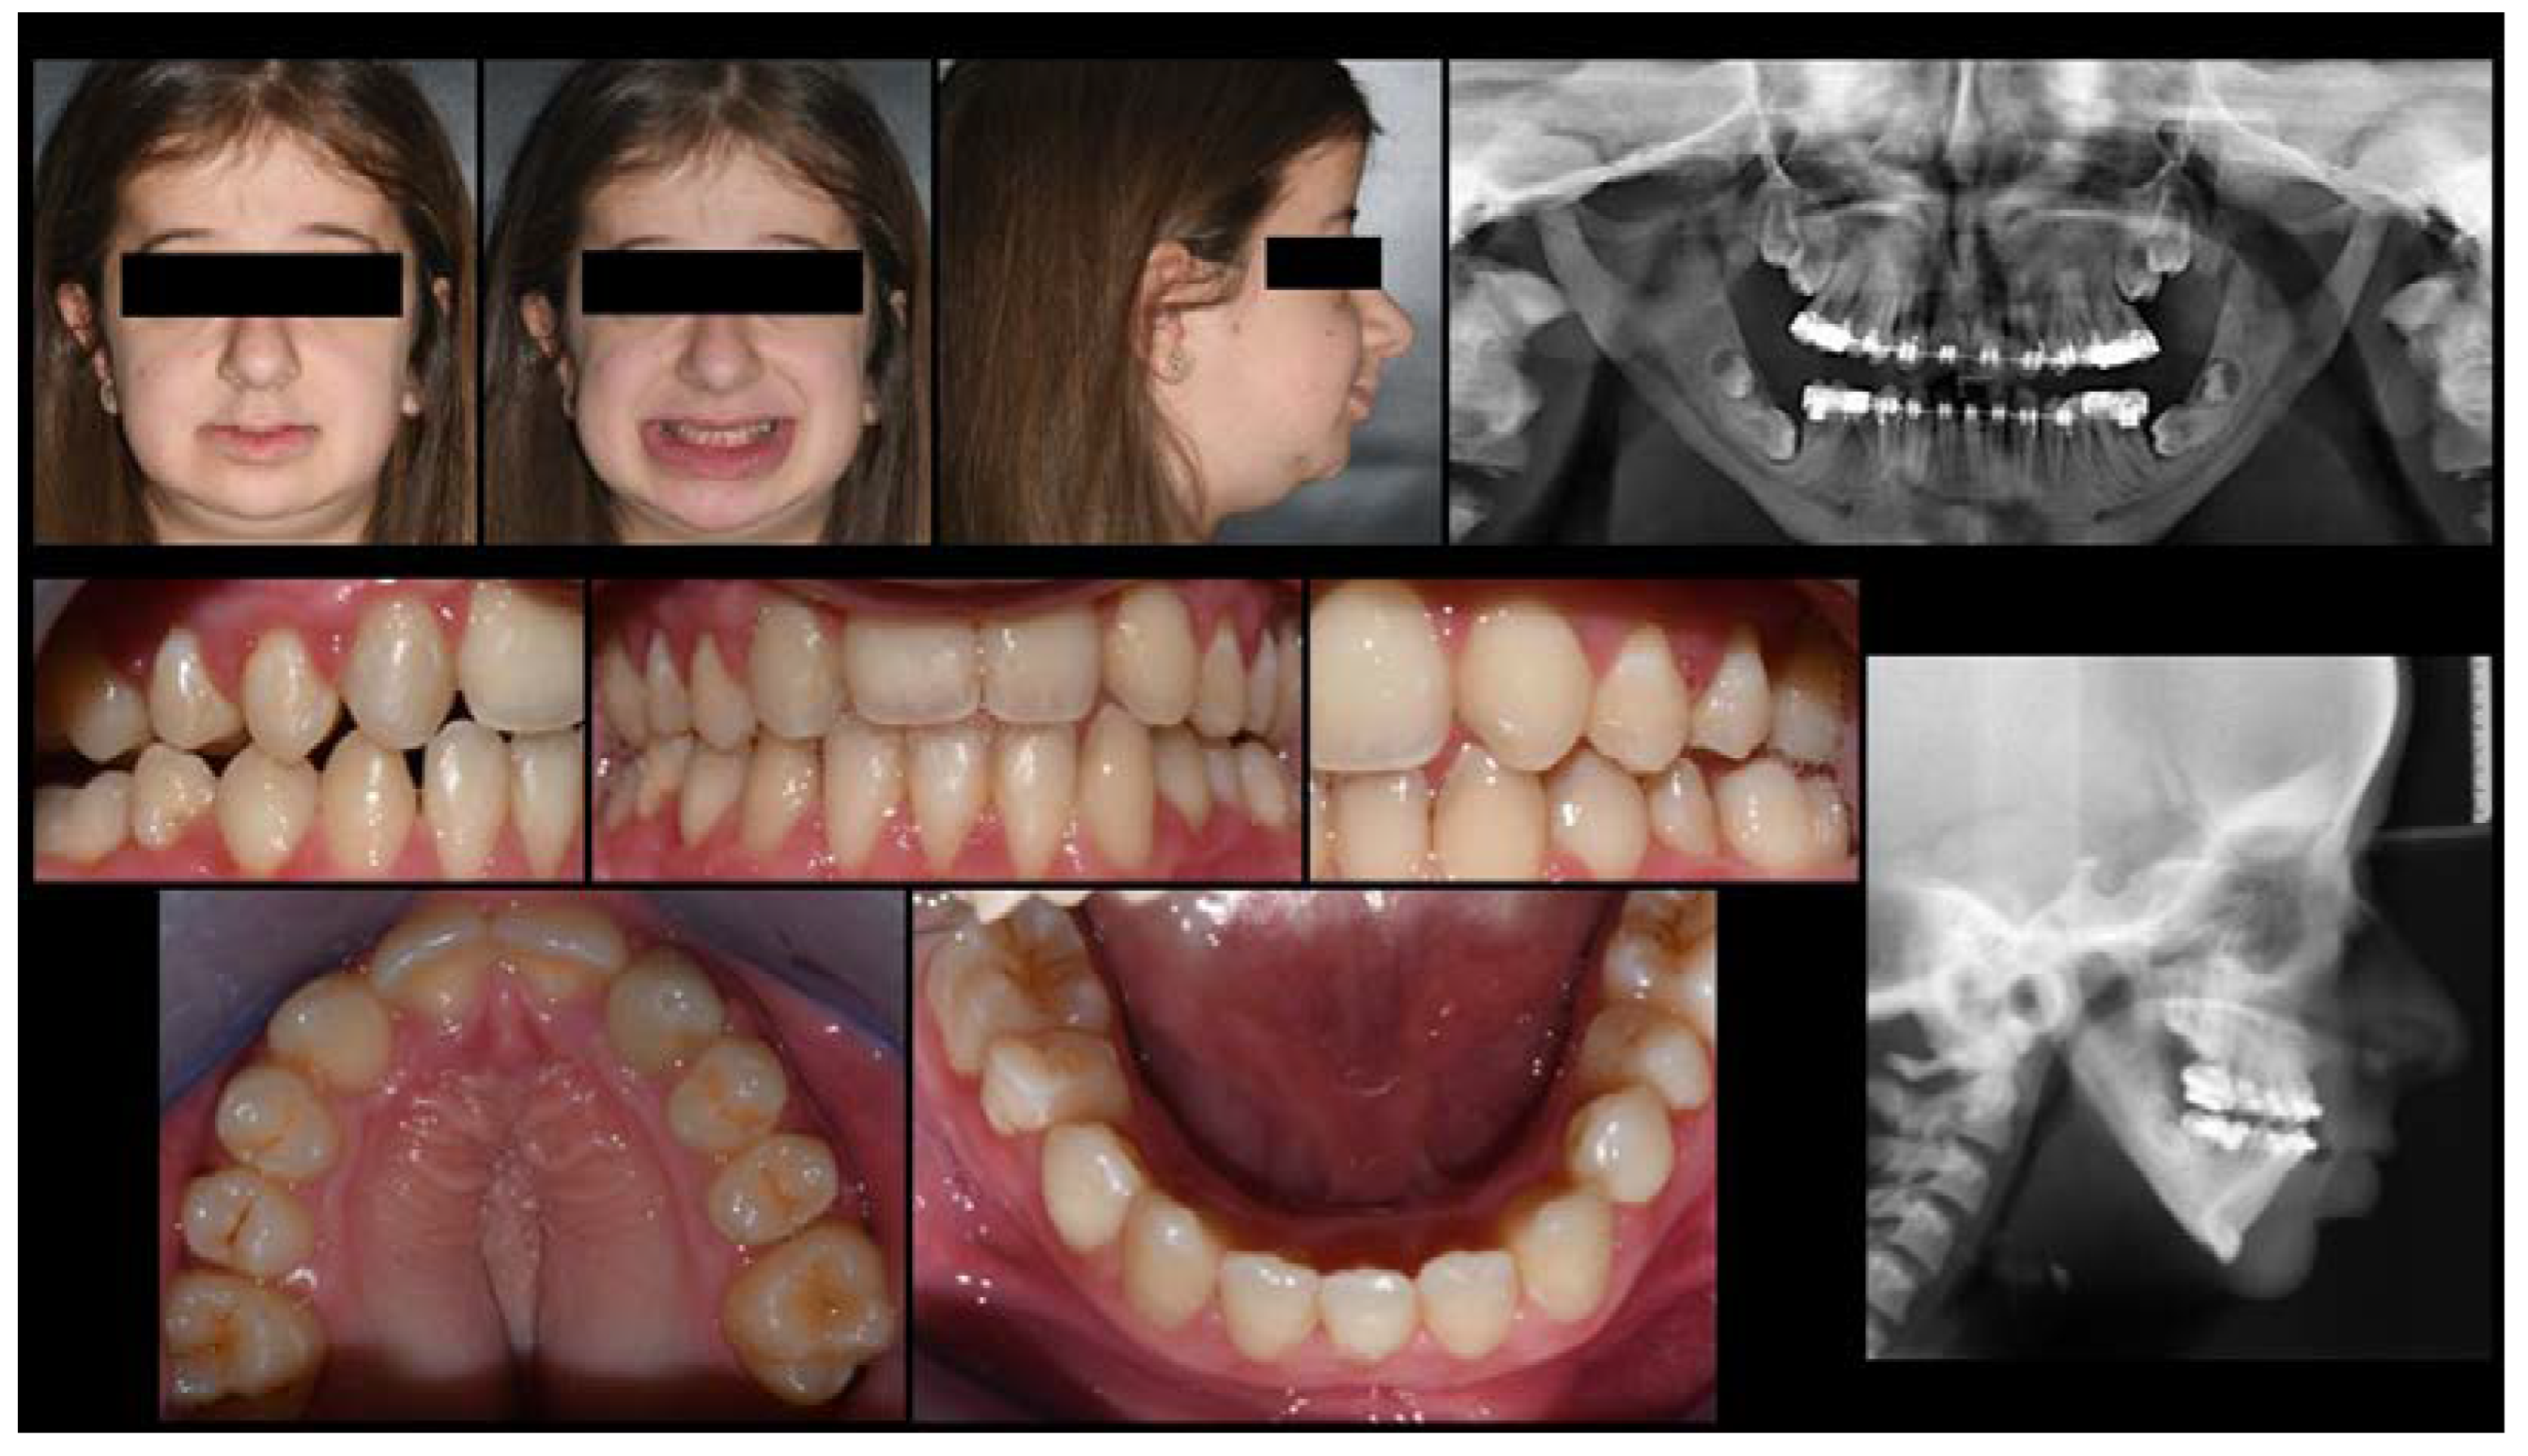

3.1. Orthodontic Results

3.2. Cephalometric Evaluations

3.3. Quantitative Point-Based Assessment of Airway

3.4. Functional Assessment of Obstructive Sleep Apnea: AHI